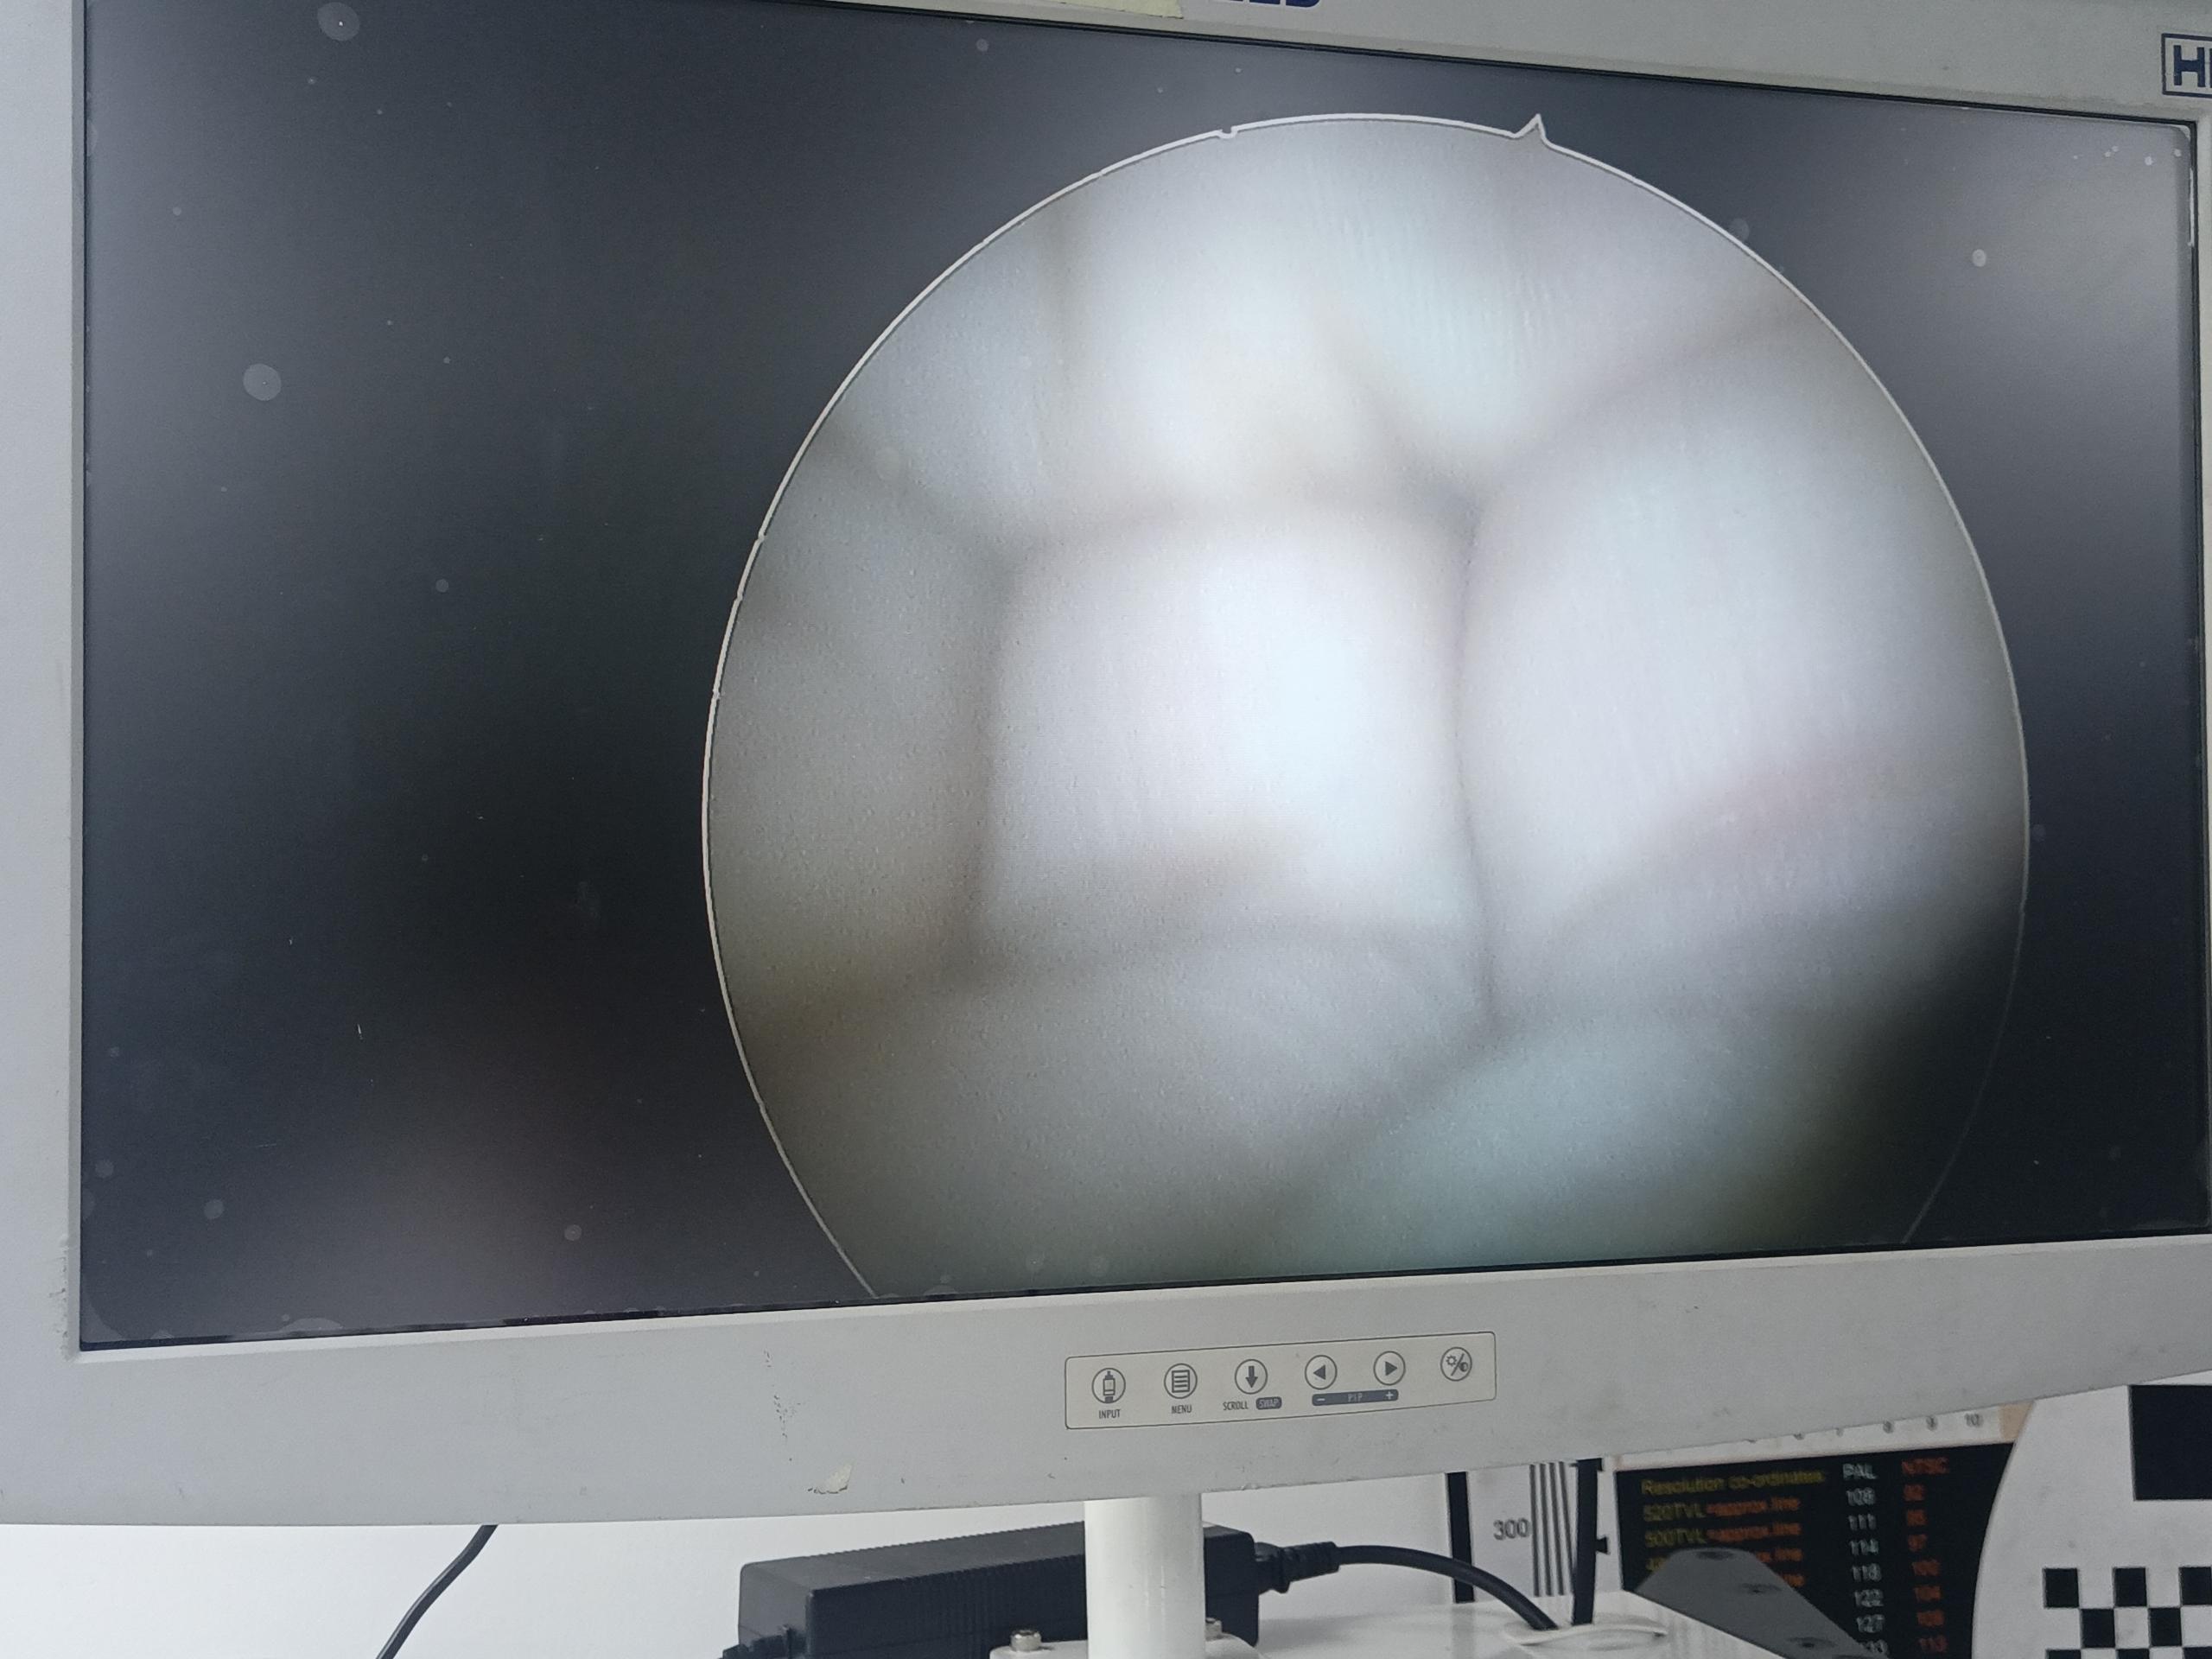

| 設(shè)備型號 | YOUSHI優(yōu)視宮腔鏡 Y5033 |

| 故障內(nèi)容 | 圖像模糊,物鏡破損,漏水腐蝕,棒透鏡腐蝕,圖像偏移 |

| 維修方案 | 更換物鏡,更換棒透鏡 ,校對圖像,內(nèi)窺鏡抗震蕩抗沖擊性能測試,內(nèi)窺鏡密封性性能檢測;內(nèi)窺鏡抗震蕩性能測試,內(nèi)窺鏡冷熱沖擊性能檢測。 |